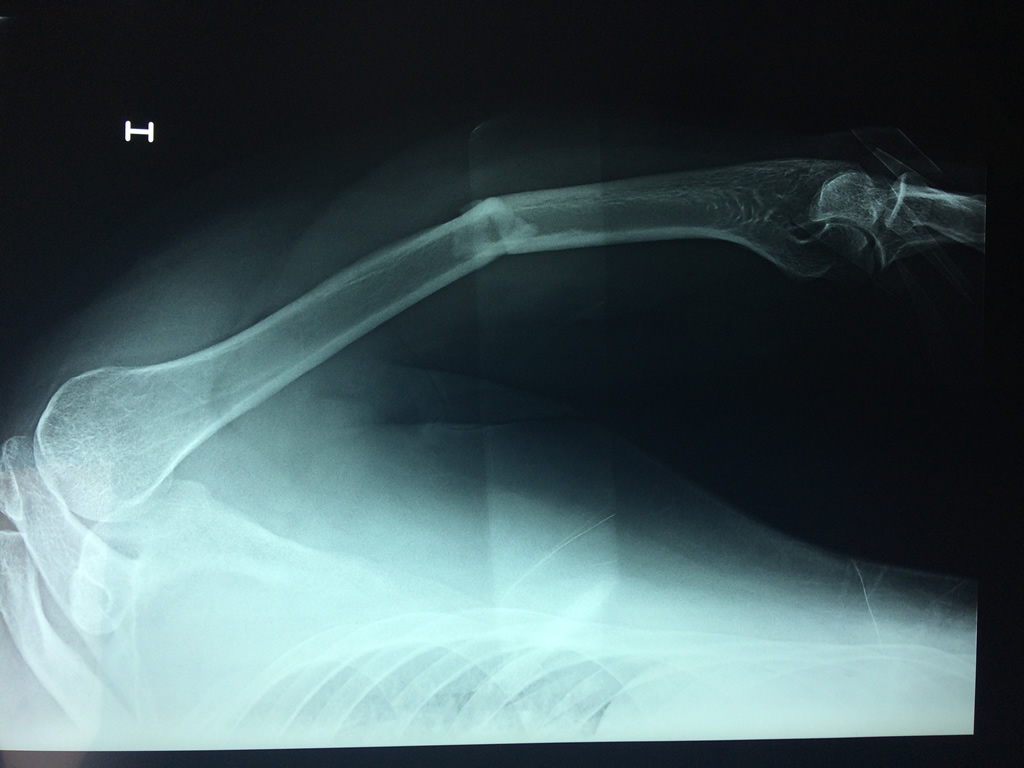

Cirugias en El Salvador - Húmero

El Húmero (en latín, humerus) es el hueso más largo de las extremidades superiores en el ser humano. Forma parte del esqueleto apendicular superior y está ubicado en la región del brazo. ... El extremo proximal del húmero tiene la cabeza, cuellos quirúrgico y anatómico y tubérculos mayor y menor.